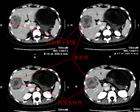

胰腺炎 胰腺炎: 是胰腺因胰蛋白酶的自身消化作用而引起的疾病。胰腺有水肿、充血,或出血、坏死。临床上出现腹痛、腹胀、恶心、呕吐、发热等症状。化验血和尿中淀粉酶含量升高等。可分为急性及慢性二种。 胆道疾病。胆囊炎,胆石症。酗酒和暴饮暴食。十二指肠乳头部病变。十二指肠溃疡或炎症。流行性腮腺炎,病毒性肝炎,腹腔手术,腹部外伤,某些药物也可引起胰腺炎发作。